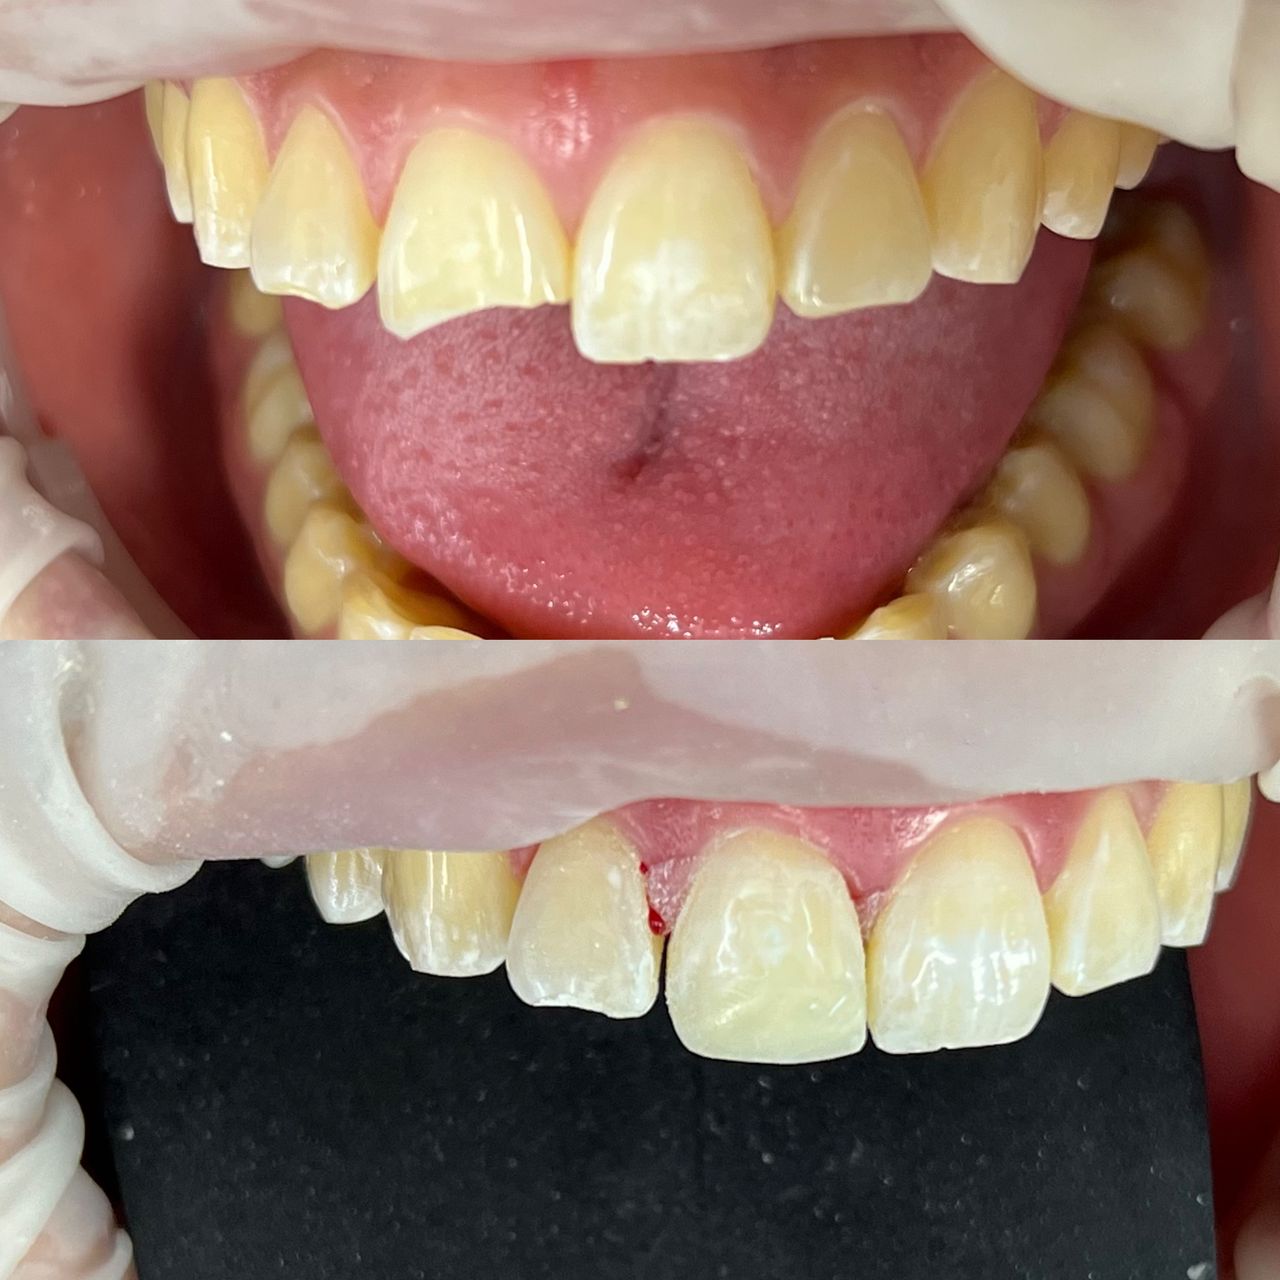

- Odontología estética

- Rehabilitación bucal